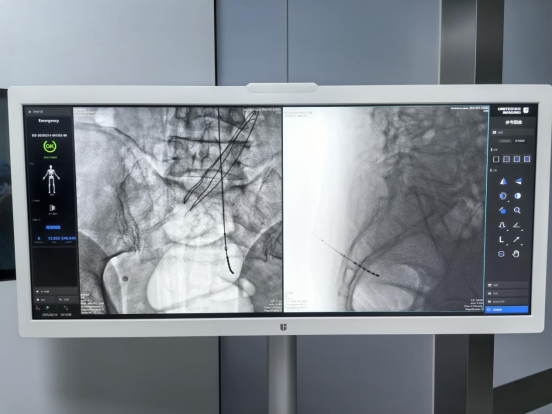

在完善相关术前检查后,孙主任为患者实施国产创新六触点骶神经调控一期电极植入术,电极植入位置精准,术中测试六个触点刺激均有效,手术顺利完成。

一期体验治疗期间,患者症状改善明显,下腹部胀痛及排尿障碍情况明显好转,经评估,患者满意度高,符合转化标准。术后约2周,患者顺利接受国产创新六触点骶神经调控二期神经刺激器置入术。术后疗效稳定,患者的心情、生活状态都有极大改善。

孙小科主任介绍,相较于传统四触点电极,国产创新六触点骶神经调控系统SacralStim增加了贴近骶神经的刺激触点个数,“低电压、高灵敏”的正负极组合临床设计理念,在相近单位长度内增加触点个数,为后期程控提供了更多组合方案。传统四触点治疗方案为16种,六触点治疗方案组合高达30种,治疗方案多样化能够为患者在长期治疗过程中提供精准疗效。另外该系统具备远场通信技术,可避免术中感染。